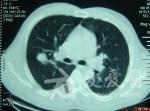

分享【一般资料】 男,44岁。 【主诉】 外伤查体发现右肺结节10天。偶有盗汗。 【辅助检查】 神经元特异性烯醇化酶偏高。 【CT表现】 右肺上叶后段斜裂胸膜及水平裂胸膜下一大一小二个(大者位于外侧)等、高混杂密度结节,内可见等密度软组织密度影及斑块状高密度钙化影,边缘规整,大结节钙化主要位于后部呈偏心性分布,前外侧肺组织内可见扇形GGO影,有胸膜凹陷征,小结节下方可见索条状影,两侧胸腔少量积液,增强大结节内等密度软组织成分有强化。 【分析思路】 中年病人,临床病人偶有盗汗,影像右肺上叶内侧较小结节病灶内有钙化,周围有卫星灶,影像高度提示为结核。右肺上叶较大结节位于叶间裂胸膜下,有胸膜凹陷征,有阻塞性肺炎,增强有强化,胸腔有积液,影像高度提示为恶性病变,所以首先想到周围型肺癌,但周围型肺癌病灶多有分叶,有毛刺,有血管集束征,实验室相关生化检查可出现异常,不太支持;结节为恶性,病人为中年男性病人,病灶属外伤查体发现,细看病灶内侧与支气管关系密切,病灶内的钙化较多,呈斑块状,呈偏心性分布,影像高度度提示为不典型类癌。1、肺不典型类癌好发于40岁以上的中老年人,临床症状无明显特异性,患者除呼吸系统症状外出现阵发性皮肤潮红、腹泻、哮喘、心悸、血压增高、满月脸等少见症状时要高度怀疑支气管肺类癌可能。2、影像学表现多为周围型单一病灶,边界清楚,分叶常见;病灶内钙化为特征表现,可以呈偏心或弥散分布,空洞少见。3、病灶较大并向周围侵犯邻近肺组织时CT可见"冰山征"表现,此征象有助于周围型肺不典型类癌的诊断。虽然确诊需要支气管镜活检和手术病理结果,但综合以上几点临床和影像学特征,仍然对肺不典型类癌的诊断提供重要的参考价值。 【CT诊断】 右肺上叶后段不典型类癌伴结核。 【鉴别诊断】 1、周围型肺癌:详见分析思路。2、肺错构瘤:CT上表现为圆形、类圆形肿块,边缘光滑,病肺交界面截然,周围的肺组织正常,典型的内钙化呈爆米花状。3、肺软骨瘤:如肿瘤较小则表现密度均匀,边缘锐利,如瘤体较大则病灶内呈不规则结节状或片状钙化灶,增强扫描无强化。肺软骨瘤多发生在下叶。肺软骨瘤可作为Carney三联征的一种征象被查出。Carney三联综合征是由肺软骨瘤、胃肠道平滑肌肉瘤和肾上腺外的功能性副交感神经瘤组成,临床上出现3种或者其中任意2种肿瘤即可诊断;该病多见于年轻女性。4、肺硬化性血管瘤:病灶肺门侧可见一尾状突起,似为尾征,故要注意与硬化性血管瘤鉴别,但本例病灶不算大,增强后应该有比较显著的强化,并可见"贴边血管征"及"肺动脉为主征",且多见于中青年女性病人。5、炎性假瘤:叶间胸膜下的病灶,与胸膜关系较密切,可呈广基相连,可有"平直征"、"向心性弓形凹陷征"及"桃尖征",病灶综含有"收缩形态"征。6、真菌感染:以继发多见,临床有引起免疫力低下的相关疾病,或有使用免疫抑制剂、激素、滥用广普抗生素等病史,影像肺内多表现为结节、纤维索条、片状与实变和空洞等多样化形式存在,实变典型的呈底部位于胸膜的楔形影,内密度均匀,边缘模糊,空洞性病灶多见,多为中心性空洞或为薄壁多房空洞,空洞内少有液平,肺曲菌病内可见曲菌球。7、肺转移瘤:病人可有原发恶性肿瘤病史,转移瘤多发多见,并且大小相差不大,边缘多较规整,转移瘤可有胸膜凹陷征,但无阻塞性肺炎表现,两肺门和/或纵隔可见有肿大淋巴结。先看病史及辅助检查如图